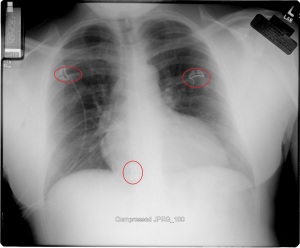

“My family and I have been the subjects of Government funded human research and/or hate crimes. These crimes are being covered-up by using the words National Security. The fact that my two minor children have the same and/or similar devices in their little bodies speaks for themselves. My sons were ages 3 and 4 when the discoveries took place. Their x-rays, blood & urine analysis present the true facts. The devices can only be introduced into the body, while being in a medical facility. All three of us were patient of the same defendant hospital.

“The CD-ROM from CCAI depicts the same images that are attached. I will bring the 01/03/2012 Simonmed Imaging CT scan which also depict foreign objets in the heart and chest.”

“Please take a look at both X-rays. Superimpose the foreign objects AKA EKG clamps and you will find that they are the same devices. when have you ever seen an EKG clamp place sideways in the abdomen? Both x-rays have been confirmed by Radiologist Louis Teresi as having foreign body reactions in the abdomen, right and left flanks.

“The obvious implant in the 2012 x-ray stands out from the others, because it at the time had not embedded into my flesh (heart).”